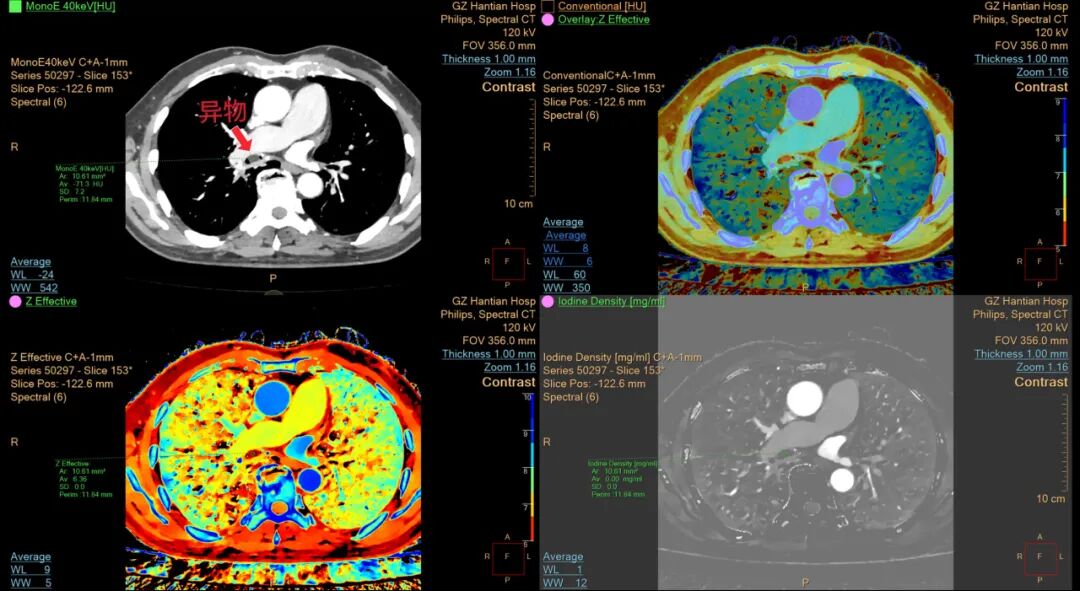

近日,73岁的杨先生(化名)因呼吸困难紧急就诊于我院呼吸与危重症医学科,经接诊医生仔细询问病史后,高度怀疑患者支气管存在异物(花生米)堵塞。因当时情况十分危急,考虑到普通CT/X光定位模糊及辨识度较差等局限,接诊医生立即决定采用能谱CT精准判断异物种类及堵塞位置,最后结合支气管镜手术成功取出异物。 能谱CT如何大显身手 两大核心优势助力精准诊疗 针对支气管异物堵塞,传统检查手段存在定位模糊、成分辨识不清等局限,可能会存在误诊、漏诊的情况。能谱CT相当于为医生配备了"透视眼"与"成分分析仪",能够精准判断异物所在位置及种类。 优势一: 精准定位——给手术装"导航" 能谱CT的"高清细节+多维视角",让医生对异物情况了如指掌: 超高清"立体透视":可生成厚度小于1毫米的薄层图像,细支气管内花生米的大小、形状均能清晰呈现。 多维度全视角观察:通过三维重建技术,医生可从冠状位、矢状位等任意角度获取图像,如同深入患者体内,精准掌握异物的位置及其与周围血管的毗邻关系。 全面评估周围组织状态:可同步检测异物是否引发炎症、水肿或早期脓肿,为术前风险预判提供依据。 有了这些信息,医生做支气管镜手术时路径更准、时间更短,患者少遭罪,并发症风险也大大降低。 优势二: 成分分析——给异物"验明正身" 这才是能谱CT的"独门绝技"!它不仅能"拍照",还能做"成分鉴定": 识别"物质指纹":不同物质(如花生、塑料、骨头、矿物质等)对X射线的吸收特性存在差异,能谱CT可精准识别这些"指纹"——例如,花生主要富含油脂和蛋白质、碳水化合物等,其特征尤为显著。 基物质"解码":通过脂/水基图等特殊图像,能谱CT可将图像中每个像素点解析为脂肪、蛋白质等基础物质的含量。花生的油脂成分在脂/水基图中会清晰显示,与肌肉、血块等组织明确区分。 确认"身份":当异物的能谱曲线与花生特征高度吻合时,即可精准判定为花生或同类油性植物异物,有效降低误诊率。 这种从"形态观察"到"成分辨识"的技术突破,使能谱CT在肿瘤诊疗、淋巴结鉴别等领域展现出显著优势,可通过组织"指纹"精准区分肿瘤类型,借助碘图分析组织血流状况,还能有效鉴别新旧血栓...... 能谱CT通过物质同源分析,实现了从形态学到成分定量的跨越,其“精准定位”和“物质同源分析”的卓越能力,如同为医生配备了“透视眼”和“成分分析仪”,尤其在肿瘤诊疗中,帮助医生“追踪根源”、制定精准治疗方案,是现代影像学的主要突破,其价值不仅在于诊断准确性的提升,更推动了个性化医疗的发展。 贵州航天医院 医学影像科专家简介 余 雷 超声、影像党支部书记,医学影像科主任,主任医师 专业擅长:从事医学影像工作30余年,在CT、MRI诊断方面经验丰富,对疑难、复杂病例有较强的综合影像诊断能力。 曾于上海市第六人民医院和第四军医大学进修学习。以第一作者发表学术论文十余篇,省级科研结题一项。现任贵州省医学会影像技术学分会委员,贵州省非公医疗机构医学影像专委会常委,遵义市医学会放射学分会常委,遵义市民营医疗机构医学影像专委会副主任委员。 吴德生 中共党员,医学影像科副主任,副主任医师 遵义市医学会放射学分会第一、二届委员,遵义市中西医结合学会委员,遵义市结核病诊疗医疗质量控制中心委员,遵义医药高等专科学校兼职副教授。 专业擅长:胸腹部CT及MRI影像诊断,主要从事肺结核、肺结节MDT影像诊断,胃肠道肿瘤诊断,尤其是结直肠癌TNM分期诊断。 贵州航天医院医学影像科简介 基本情况 贵州航天医院医学影像科是集医疗、教学、科研为一体的现代化科室。科室设备先进,技术力量雄厚,经验丰富,人员结构合理,已全面实现数字化,2023年获批遵义市重点专科建设科室。科室业务覆盖普放、CT、MRI检查诊断,2024年引进贵州省首台飞利浦256排光谱CT。科室现有医技护等人员37人,副高级以上职称9人。是遵义医科大学、遵义医药高等专科学校、黔南民族医学专科学校、毕节医学专科学校等院校实习基地。科室为贵州省医学影像结果互认单位,与县级、乡镇及民营医院等建立了专科联盟及医联体,开展了远程影像诊断和技术对口帮扶工作,承担遵义市第二城市医疗集团影像中心建设工作。 专科特色 (一)光谱CT成像技术 应用范围:在心血管、肿瘤、神经等系统的疾病诊断方面有其独特的价值,能够发现隐匿性肿瘤病灶,利用光谱曲线、碘定量测量等,可以分析肿瘤的良恶性,多发病灶的同源性;还能显示心肌缺血灶,对血管斑块进行定量定性分析等等。 (二)胸痛CT血管联合成像技术 应用范围:能够同时进行冠状动脉、肺动脉和胸主动脉成像,诊断冠心病、肺动脉栓塞、主动脉夹层等急危病变。 (三)CT左心房+肺静脉成像技术 应用范围:能在心房颤动术前提供左心房和肺静脉的解剖细节、肺静脉远端分支变异以及左房和食管周边组织之间的关系等很多有价值的信息,从而指导房颤射频消融的顺利进行。 (四)乳腺肿瘤MRI扫描TIC曲线分析 应用范围:对乳房肿瘤、结节的良恶性程度进行分析。 (五)颅脑MRI及CT灌注成像 应用范围:诊断急性脑卒中区分核心梗死区和半暗区,脑肿瘤,烟雾病Alzheimer病,脑供血不足等颅脑血管及脑组织异常引起的疾病。